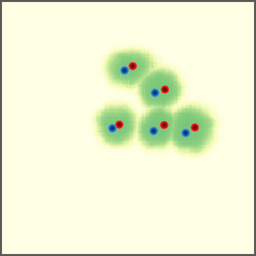

POI Selection. The first step of the proposed approach requires selecting a set of POIs to set up a point-to-point correspondence. In this experiment, we investigate different POI selection strategies. First, we investigate directly using landmarks as the POIs since they usually have strong semantic meaning and can be annotated before the intervention. Second, we also investigate an automatic solution that uses the Harris corners as the POIs to avoid the labor work of annotation. Finally, we try random POI selection.

As shown in Figure 7 (a), we find our approach is prone to overfitting when trained with landmark POIs. This is actually reasonable as each CBCT volume only contains about a dozen of landmarks, which in total is about 3,00030003,000 POIs. Considering the variety of the field of views of our dataset, this is far from enough and leads to the overfitting. For the Harris corners, a few hundreds of POIs are selected from each CBCT volume, and we can see an improvement in performance, but the overfitting still exists (Figure 7 (b)). We find the use of random POIs gives the best performance and generalizes well to unseen data (Figure 7 (c)). This seemly surprising observation is, in fact, reasonable as it forces the model to learn a more general way to extract features at a fine-grained level, instead of memorizing some feature points that may look different when projected from a different view.

Refer to caption

(a) landmark

(b) Harris corner

(c) random

Figure 7: Training and validation losses of different POI selection methods.